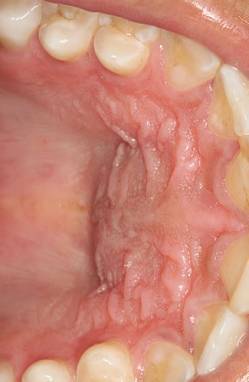

La inflamación del paladar puede ser muy dolorosa y molesta. Algunos de los síntomas incluyen la aparición de ampollas, dolor al tragar y un aspecto rojizo e hinchado del paladar. Aquí te presentamos algunos remedios naturales y consejos prácticos para tratar eficazmente la inflamación del paladar.